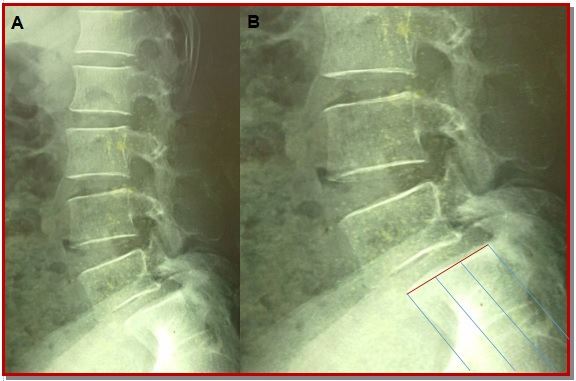

Spondylolisthesis is forward slipping of upper vertebra in relations to its lower one, commonest is L4-L5. The ideal surgical treatment of spondylolisthesis is still controversial. Posterior lumber interbody fusion with pedicle fixation is one of treatment choices for the lumber spondylolisthesis. Forty patients who operated through posterior lumber interbody fusion and pedicle screw fixation by single surgeon was included from January 2012 to March 2015. Periodical follow-up was done both clinically and radiologically up to 6 months. Patient outcome was completed based on pain relief graphic rating scale and Oswestry disability index. In our series, the excellent outcome were 25 patients (62.5%), good were 12 patients (30%), and fair were 3 patients (7.5%). There were no poor outcome and no new neurological deficit. This study concludes that posterior lumber inter-body fusion with pedicle is an effective treatment for the lumber spondylolisthesis. It helps to maintain the biomechanics, associated with less complication and improve the quality of life of patient.